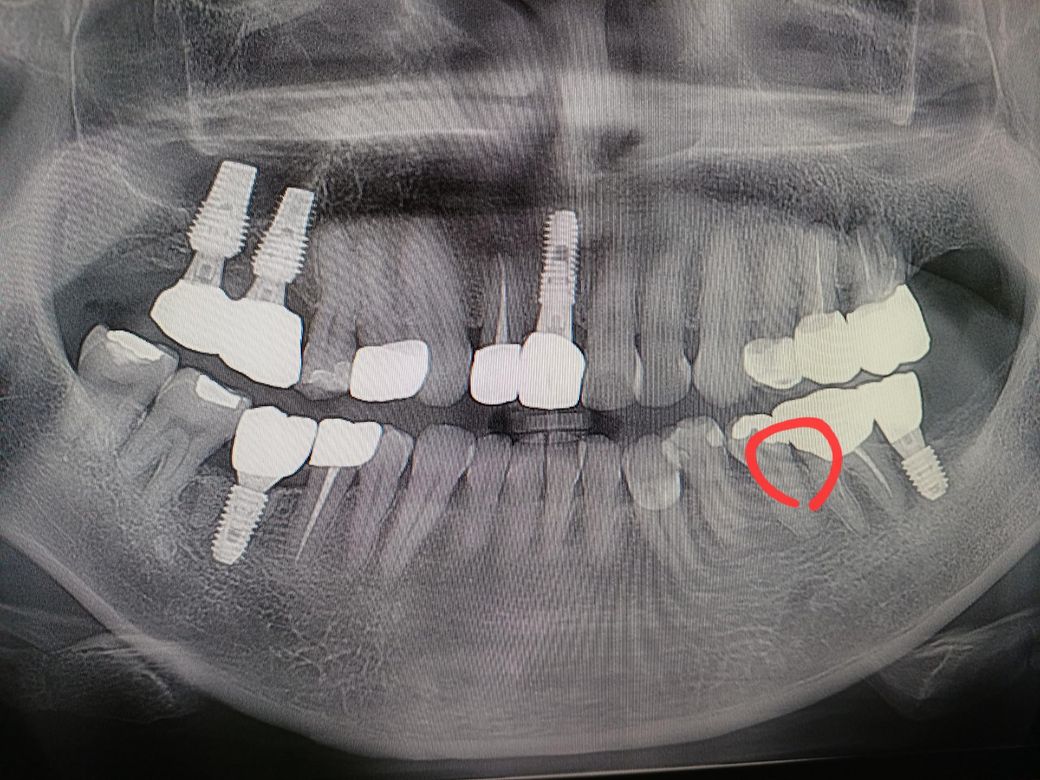

갑자기 신경치료 한 크라운 치아가 씹을때 약간 통증 있고 씹고나면 약간 욱신거리는데 8개월 전 에 찍은 사진보다 좀더 시커멓게 나오는데 충치인지 충치때문에 아픈건지 8개월만에 저렇게 변하는지 궁금합니다

저이빨이 3~4년전에 뒤쪽이빨 임플란트할때 혼자 힘을 많이받을때는 아픈적있었는데 임플란트하고 그뒤로는 몇년간 안아프다가 이제 조금씩 욱신거립니다 문의드립니다

파노라마 사진이 하나가 좌우반전이 되어 있네요

증상이 있으면 치근단 엑스레이 찍어보면 좋을 것 같습니다

충치가 잘 생길 조건이긴 하네요